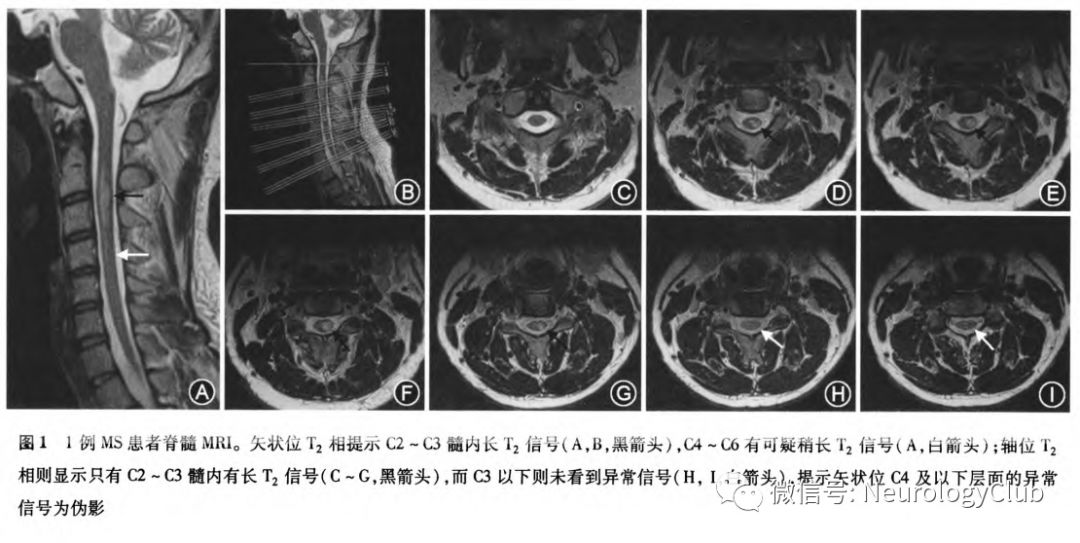

影像上NMOSD颅内病灶多分布在AQP4受体高表达区域,如间脑、三脑室周、脑桥被盖、胼胝体、极后区等但少数患者影像可以不典型,如脑内呈大片肿瘤样占位或多发片状病灶,影像上类似瘤样炎性脱髓鞘病变或急性播散性脑脊髓炎,需检测AQP4-IgG以协助诊断NMOSD脊髓受累的影像学特点以横轴位脊髓中央病灶居多,而MS多为偏心病灶且受累绝大多数少于2个椎体节段。脊髓病灶要注意把轴位及矢状位影像结合判断,如图1所示作者单位1例患者,矢状位C2-C7节段有长T2信号,超过3个椎体节段,似乎符合NMOSD,但轴位上仅在C2-C3髓内有明确长T2信号,提示矢状位C4以下异常信号为伪影(脑脊液波动),该病例脑脊液寡克隆区带阳性、AQP4-IgG阴性,确诊为MS。黄鑫等总结22例表现为超长节段(≥10个椎体节段)脊髓炎的NMOSD,可见NMOSD多表现为长节段脊髓受累MS颅内病灶多为脑室旁垂直分布的卵圆形病灶,一般不出现在AQP4受体高表达区域,病灶可以在胼胝体周围,而NMO病灶可以胼胝体上。此外,MOG相关的NMOSD与AQP4相关的NMOSD影像也有不同。